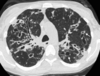

18

A

Patrón intersticial reticular